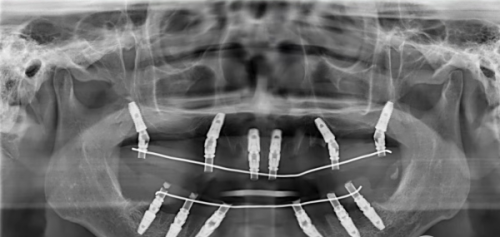

合肥美奥口腔医院拥有正规的资质,是一家值得信赖的口腔医疗机构。它是连锁品牌,在口腔医疗行业有着较高的有名度和良好的信誉。医院的医生团队实力雄厚,他们都具备丰富的临床经验和专精的知识技能。在治疗过程中,医生会根据患者的具体情况,给出清晰的医学建议,让患者对自己的病情和治疗方案有更清楚的了解。这种专精和负责的态度,赢得了顾客的一致好评。

合肥美奥口腔医院是正规的二级齿科医院。作为连锁品牌,它有着统一的管理和规范的服务流程。医院经常会推出一些项目优惠活动,让患者能够以更实惠的价格享受到优质的口腔治疗服务。医院的医生团队不仅实力强,而且服务态度也非常好。他们会耐心地解答患者的疑问,关心患者的治疗感受,让患者在治疗过程中感受到温暖和关怀。